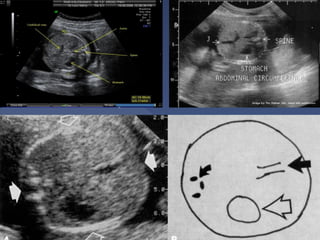

Landmarks:

o Spine + rib

o Stomach

o Part of portal

vein

o Picture should

be as round as

possible

 The single most important measurement

to make in late pregnancy

 It reflects more of fetal size and weight

rather than age.

 Serial measurements are useful in

monitoring growth of the fetus.

 AC measurements should not be used

for dating a fetus.

 It is also a mandatory measurement.

Plane

 The best plane is the one in which the portal

vein is visualized in a tangential section.

 The plane in which the stomach is visualized

is also acceptable.

 The outer edge of the circumference is

measured

 On screen computer-generated elliptical

measurements probably yield the best

results